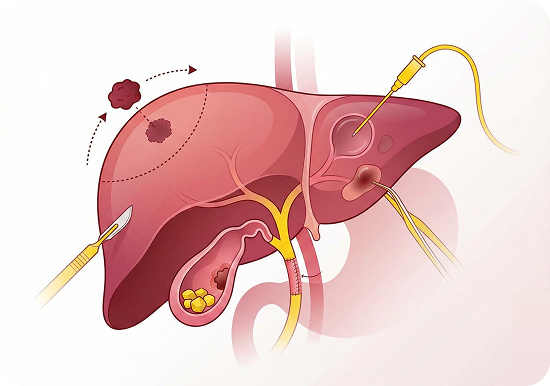

Biliary & Liver Surgery

- Hepatectomy for liver tumours and metastases

- Bile duct resections and reconstructions

- Surgery for bile duct injuries, strictures, and gallbladder stones

- Management of gallbladder cancer

- Liver cyst and abscess drainage procedures